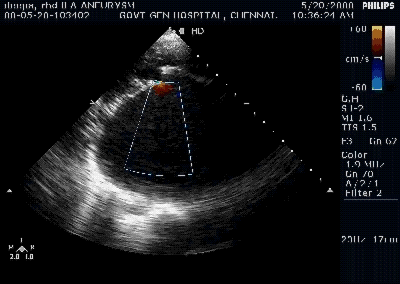

Rheumatic mitral valve prolapse

- This could be more common than we realise.

- It can be true or pseudo.

- True prolapse occur due to chordal weakening or lengthening .

- In chordal disruption the leaflet tips usually become flail

Since rheumatic process fixes the PML first , the AML appear to overshoot the plane of PML and appear as prolapse.(Pseudo )

The sail like AML commonly directs the jet posteriorly and laterally .(Murmur conducted to axilla and back )

It is rare for PML to prolapse in RHD , if it does occur , it directs the jet anteriorly (murmur conducted to aortic area mimic AS !)

It is rare to see a perfect central jet in RHD . presence of Central jet is a good sign to consider mitral valve repair.